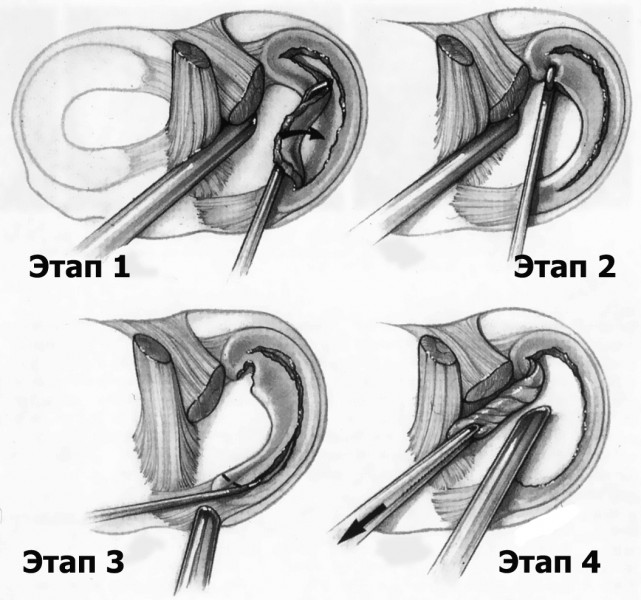

Якщо такі епізоди повторюються, виникає необхідність в операції з видалення розірваної частини меніска. Це нескладна і безпечна операція, яку виконують через проколи шкіри під контролем артроскопа - тонкого оптоволоконного зонда діаметром близько 0,5 см, до якого приєднані відеокамера і джерело світла.

Під контролем відеозображення на моніторі відірвану частину меніска відсікають і видаляють.